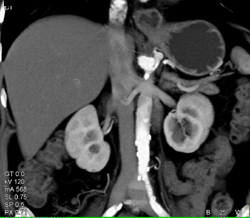

Hepatic Artery Stenosis S/P Liver Transplant